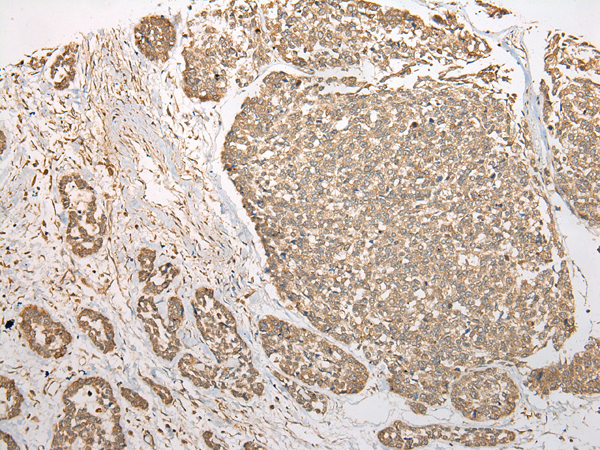

分类: 科研抗体货号: P09405别名: sen15; C1orf19应用: WB,IHC反应种属: Human, Mouse